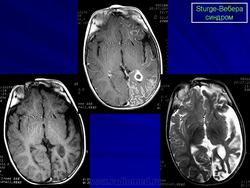

Магнитная резонансная томография пациента с болезнью Штурге - Вебера

Магнитная резонансная томография пациента с болезнью Штурге - Вебера